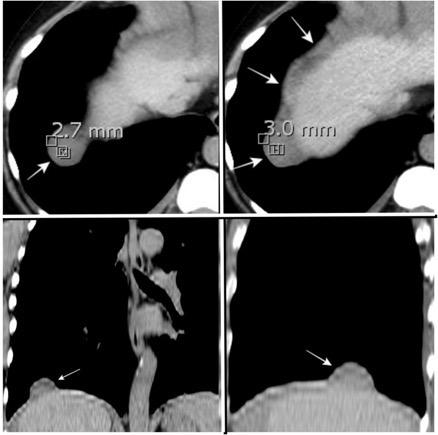

(“Dangling sign”)

TC. Mejor con multicorte. (reconstrucciones).

Asociación: Aire en pared.

Fracturas costal .Rotura esplénica. Neumoperitoneo.

Diafragma discontinúo Herniación de la grasa omental

Desser TS et al.The dangling diaphragm sign: sensitivity and comparison with existing CT signs of blunt traumatic diaphragmatic rupture. Emerg Radiol 2010